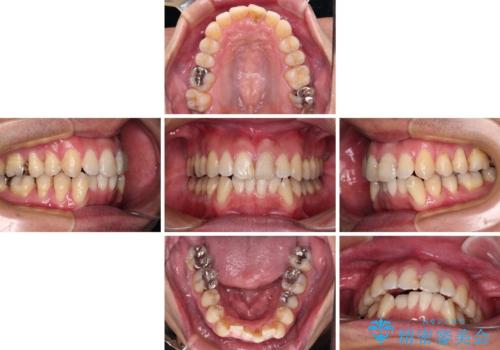

下顎にワイヤー装置を装着し、暫くしたところでやはりインビザラインにて矯正治療をしたいとのことで、インビザラインに切り替えました。

短い期間でしたがワイヤー装置を使用したことでデコボコが解消されたため、インビザラインの比較的短い期間で矯正治療を行うことができました。